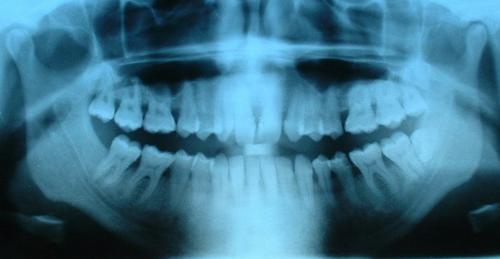

Kiedy na zębach pojawiają się dziwne plamy, jaśniejsze może to być oznaka fluorozy. Nadmiar lub Niedobów fluoru w organizmie może być widoczny wielorako. dentysta olsztyn zwraca uwagę na ten efekt widoczny po naszym uzębieniu – a więc na owe – opisywane plamy.

Jaśniejszych plam na zębach nie da się już cofnąć, należy jednak zrobić wszystko by nie rozprzestrzeniały się one na szersza skalę. Fluor znajduje się w dużej części pokarmów jednak plamy na uzębieniu – jak twierdzi dentysta olsztyn mogą wynikać z używania przez nas past do zębów o znacznie większej dawce fluoru niż ta zalecana.

Wtedy też należy jak najszybciej taka pastę odstawić, gdyż może to prowadzić do całkowitego zaniku warstwy ochronnej zęba – szkliwa, a przy tym do osłabienia zęba już od korzenia. Dentysta olsztyn ma wiele zasad, wedle których leczy fluorozę i właśnie dentysta olsztyn nie my sami – musi zdecydować, która z nich wybrać. To bowiem bardzo częsty błąd, że staramy się sami leczyc przez co możemy sobie dodatkowo zaszkodzić..